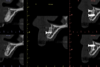

Indication de la greffe |

Indication de la greffe

Sect 22, 5 mois plus tard